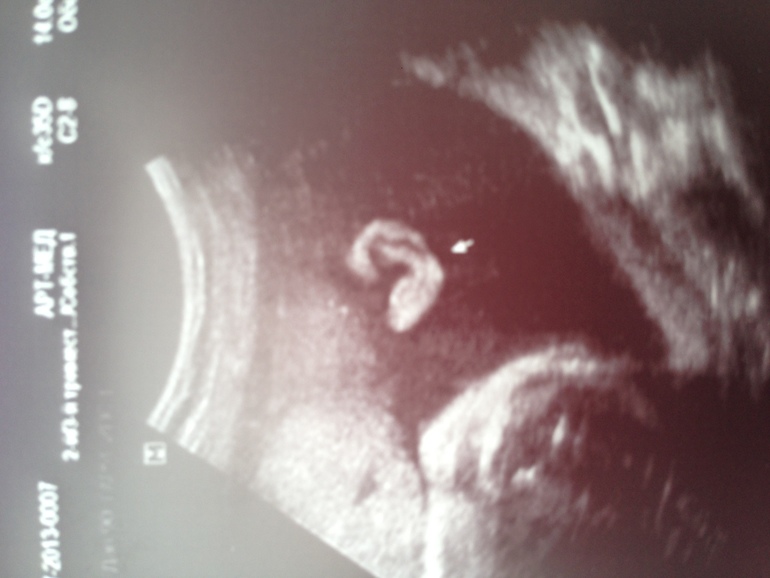

а это наше узи! доктор нам сделал снимок ушка и волосиков)

Красотищщщщщаааа!!!! В ушко влюбилась)))) и сразу косы плести) Здорово!!!!!